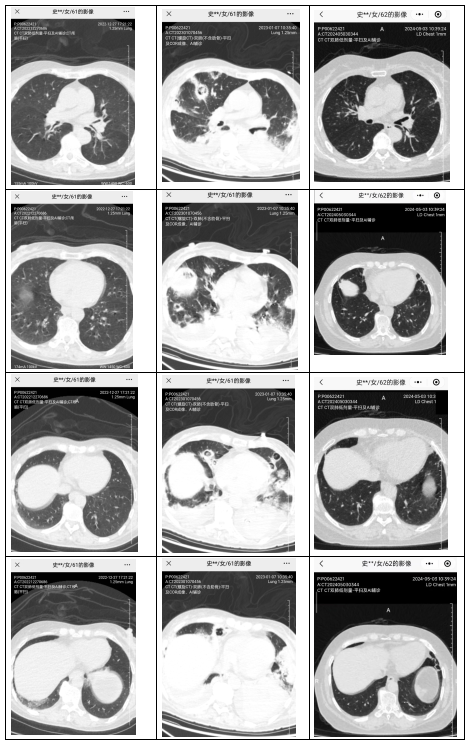

患者于2022年12月27日因“咳嗽2天,恶心、呕吐伴意识不清1天”入院。急诊检查提示多项指标严重异常,其中pH 6.87,血糖 47.64mmol/L,血钾 6.66mmol/L,白细胞 32.73×109/L,急诊以酮症酸中毒收住急诊重症监护病房。入院后经积极救治,血糖得到控制,酸碱及电解质失衡得以纠正。12月31日出现呼吸衰竭加重、休克,给予气管插管、呼吸机辅助呼吸、血管活性药物治疗。1月7日复查肺CT示双肺新出现多发空洞样病灶,提示侵袭性肺曲霉菌感染。经伏立康唑、两性霉素B等抗感染和综合治疗后病情逐渐好转;针对下肢深静脉血栓给予抗凝治疗;针对脏器功能异常给予对症治疗;针对长期卧床、活动能力差给予康复治疗;经治疗后患者病情平稳并出院。定期复查,曲霉病灶逐渐缩小。2023年7月因症状加重、病灶较前增大再次住院。行超声引导下经皮肺穿刺检查病理诊断为机化性肺炎。加用激素等药物治疗;针对气管内占位进行电子支气管镜下圈套切除。院外定期对患者进行随访管理,患者恢复了生活自理能力,肺部病灶逐渐吸收减少并稳定,但随着药物的减量,病灶时有反复,故不断调整药物,保持维持病灶稳定的最小剂量药物。目前已随访2年余,病情稳定。

图1:各时期影像学变化对比图